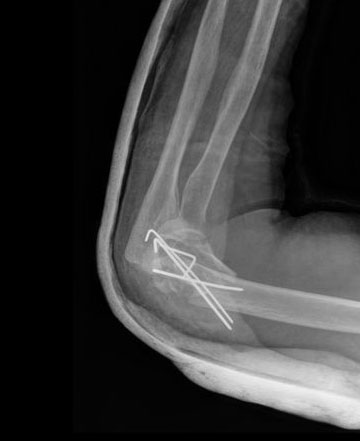

Fractura de olécranon con osteosíntesis.

Fractura supracondílea de codo. Tratamiento con agujas.